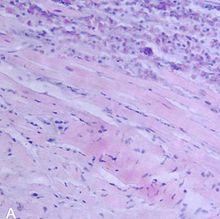

A microscope image of myocarditis at autopsy in a person with acute onset of heart failure | |

The gold standard is the biopsy of the myocardium, in general done in the setting of angiography. A small tissue sample of the endocardium and myocardium is taken and investigated. The cause of the myocarditis can be only diagnosed by a biopsy. Endomyocardial biopsy samples are assessed for histopathology (how the tissue looks like under the microscope: myocardial interstitium may show abundant edema and inflammatory infiltrate, rich in lymphocytes and macrophages. Focal destruction of myocytes explains the myocardial pump failure.[10] In addition samples may be assessed with immunohistochemistry to determine which types of immune cells are involved in the reaction and how they are distributed. Furthermore, PCR and/or RT-PCR may be performed to identify particular viruses. Finally, further diagnostic methods like microRNA assays and gene-expression profile may be performed.